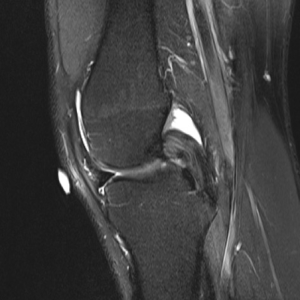

The symptomatology of LCL injury includes swelling, lateral joint line pain, difficulty ascending and descending stairs, and problems with cutting or pivoting. Patients classically ambulate with knee hyperextension or have a varus thrust gait. Lateral joint line tenderness also can occur and patients typically have opening with varus stress at 30 degrees of knee flexion. If there is varus instability at both 0 and 30 degrees, concomitant ACL and/or PCL injury is likely. If patients have increased tibial external rotation at 30 degrees, a combined LCL and PLC injury is probable. A careful neurovascular exam is important, as common peroneal nerve injuries can occur. Grading of the LCL as well as the PLC are quantified by the amount of lateral gapping with varus stress where grade I is defined at 0–5 mm opening, grade II is 5–10 mm, and grade III is >10 mm. Grade I and II indicate a partial tear, while grade III represents a complete tear. Radiographic analysis includes AP, lateral, and varus stress views while MRI is the imaging method of choice to provide information on the location and severity of the soft tissue injury (Figure 2) (7). Although posteromedial in anatomic location, interest in the posteromedial capsular attachment to the medial meniscus has grown, as a tear here, coined a ramp lesion, has been shown to possibly impart important rotational stability as well (Figure 3) (8). With injury to the PLC, meniscocapsular separation medially can occur and also should be investigated. Currently, no physical examination has been found to be sensitive or specific in diagnosing ramp lesions.

Surgery is indicated in grade III injuries, patients with rotatory instability (indicating both an LCL and PLC), and posterolateral instability (indicating LCL/PLC and ACL/PCL injuries). Controversy exists and it is not agreed upon in regard to the best repair and reconstruction sequence of these complex injuries. Improved outcomes result with acute surgery, as long as the soft tissue envelope allows. Successful outcomes have been show if surgery is done within 2 weeks, using suture anchors for avulsion injuries and suture repair alone for those of the midsubstance. In isolated LCL reconstruction, patellar tendon autograft has resulted in good outcomes. In LCL with popliteofibular ligament reconstruction, figure of eight Larson technique is utilized where a hamstring graft is passed through a fibular head bone tunnel which is consequently anchored to the lateral femoral anatomic origin. Another option is the transtibial double-bundle technique. Here, an allograft of the Achilles tendon is fixed to the femoral anatomic origin, and then tendon is split with half then being secured to the fibular head through a bone tunnel, while the other half is attached to the posterior tibia. A thorough physical exam is crucial for prompt diagnosis of complex lesions as this likely improves outcomes (10). Again, knee instability secondary to the improper healing of these injuries are likely to be pain generators and may lead to rotatory instability. The more recent identification of ramp lesions and their possibly role in knee stability has led some to advocate for fixation of these with the possibility that neglect of these lesions may be a cause of failure of ligament reconstruction and continued pain (Figure 3) (8).